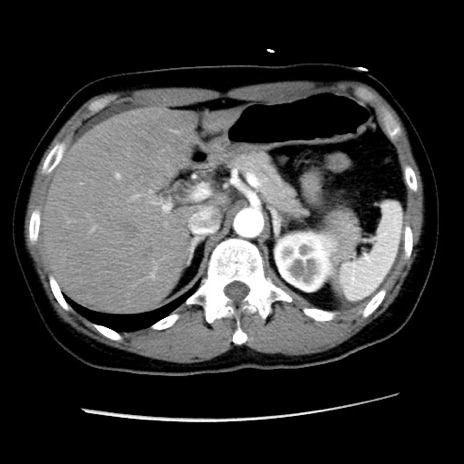

症例10(横断像)

【症例】 50歳代女性

【主訴】 腹痛

【現病歴】前日生レバーを食べた。今朝に排便あり。 昼前に突然発症の腹痛を生じ、当院救急外来を受診した。

【既往歴】 子宮筋腫にてで子宮全摘後

【身体所見】 意識清明、腹部:平坦、軟、下腹部やや左を中心に圧痛・反跳痛あり、筋性防御あり

【データ】WBC 7800、CRP 0.07